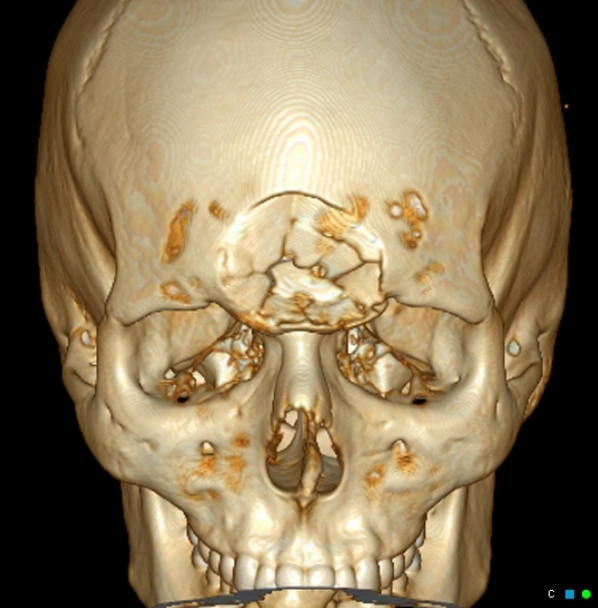

Gãy xương sọ trong tổn thương không do tai nạn (Skull fracture in Non-Accidental Injury - NAI)

16/03/2026